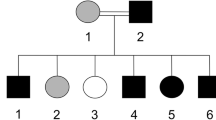

The recommendations of the Declarations of Helsinki were strictly followed for the approval of the study from the Research and Ethical Committee of Kohat University of Science and Technology (KUST), Khyber Pakhtunkhwa, Pakistan. Informed written consent was obtained from the affected and unaffected participants. A five generational pedigree diagram was constructed after a thorough interview of the unaffected mother (III-4). The pedigree showed an autosomal recessive mode of inheritance (Fig. 1A). Venous blood samples were collected from seven members of the family, including two patients (IV-4, IV-5) and five phenotypically unaffected individuals (III-4, IV-1, IV-3, IV-7, V-1). The extraction of genomic DNA from whole peripheral blood was performed by using the GeneJET Genomic DNA extraction Kit (Thermo-scientific, Lithuania), strictly following the manufacturer’s protocol.

(A) Pedigree of the family where SLC24A4 variant c.1192C > T segregates in an autosomal recessive fashion. The asterisks show tested individuals. The red arrow indicates the index patient, who was subjected toexome sequencing. T shows the disease-allele while C is the wild-type presentation (B) The representation of amelogenesis imperfecta in the patients. (i), (ii), and (iii) are the clinical features of patient IV-4 showing yellow-brown discoloration, (iv) Orthopantomogram (OPG) of the patient IV-4 showing thin layer of enamel, high radio-density and distinction from the dentin, while (v) and (vi) are the clinical photographs of the patient IV-5 showing creamy type of discoloration, attrition and dental caries

Sanger sequencing was used to check the segregation of these variants with the disease. The homozygous missense variants in PSPH, CHCHD2, BNC2 did not segregate within the family while the homozygous nonsense variant (c.1192C > T; p.Gln398*) in SLC24A4 revealed its co-segregation in the family (Fig. 2A). The DNA sequencing results of this cohort showed three forms of genotypes for this variant, heterozygous (C/T) (III-4, IV-3, IV-7), homozygous (C/C) wild-type (IV-1, V-1) and homozygous (T/T) mutant (IV-4, IV-5) (Fig. 1A). A ClinVar (https://www.ncbi.nlm.nih.gov/clinvar/variation/689492/) accession number (VCV000689492.1) for this variant has been allocated.